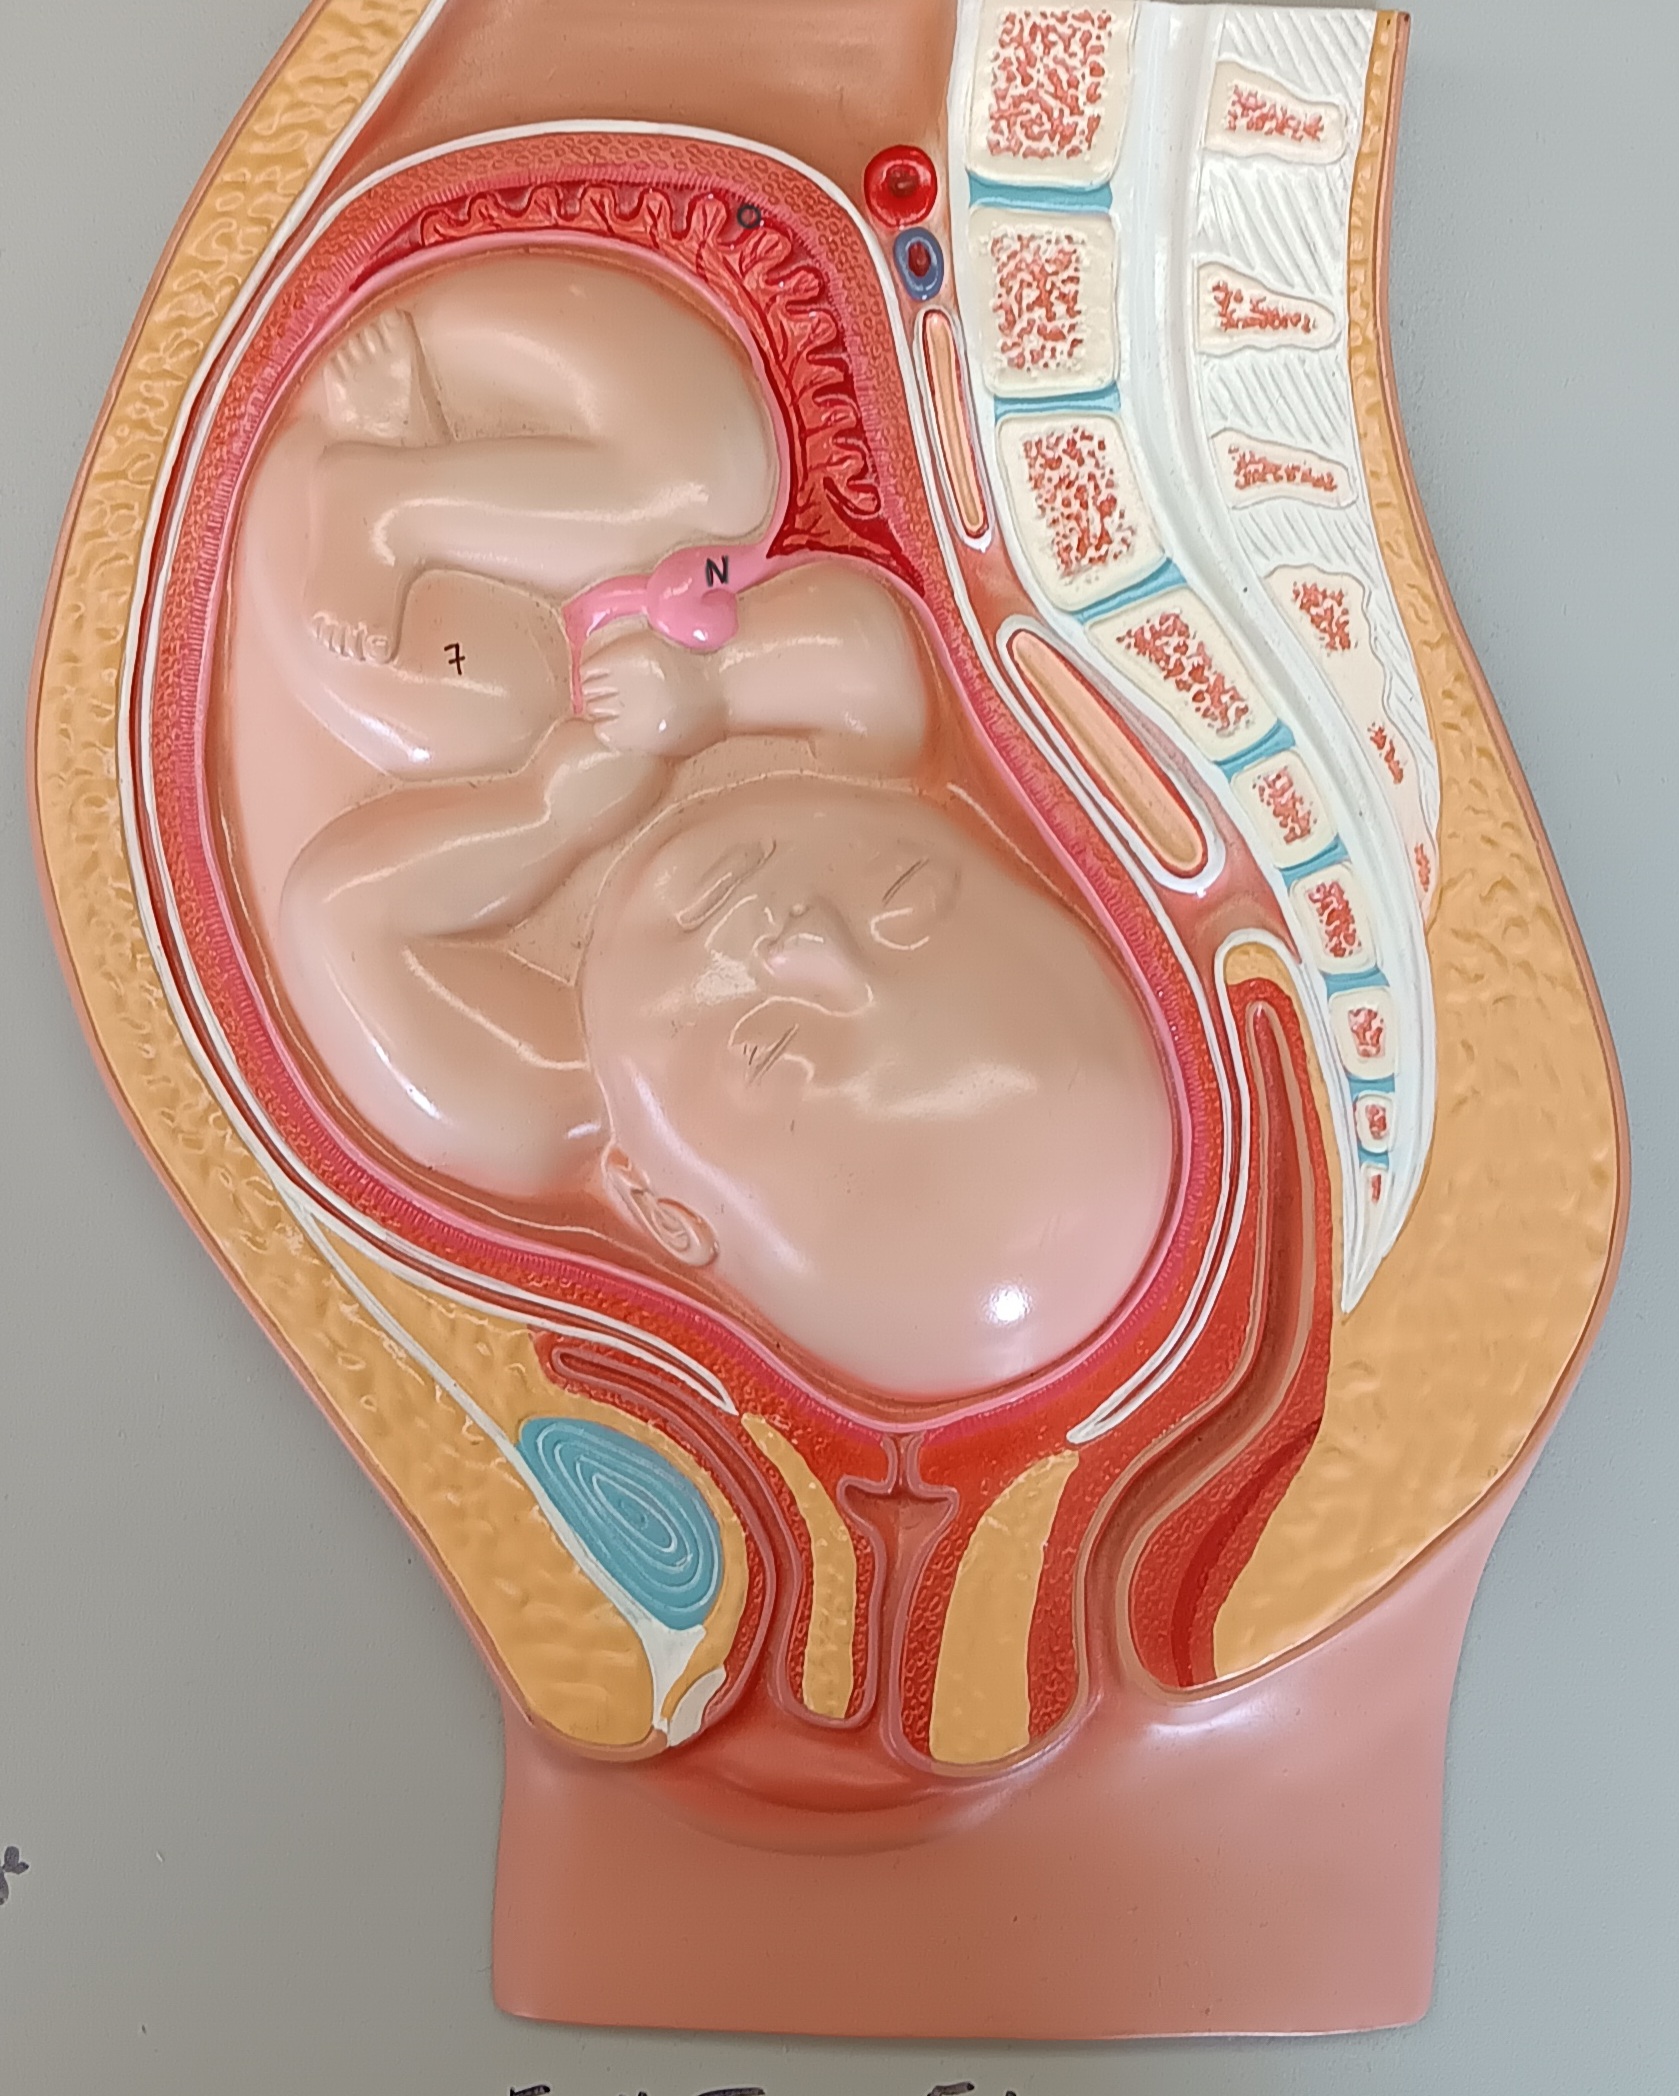

umbilical cord

n

placenta

o